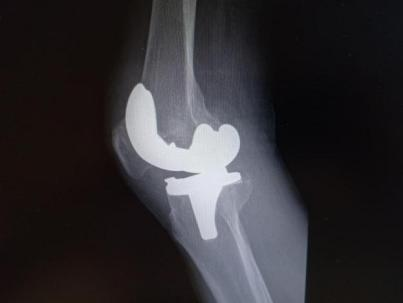

4月23日,贵州航天医院第58次晨读会由我院骨科副主任医师张艳金作学术交流,他以“加速康复指导下的快速手术”为题,详细讲解了老年股骨粗隆间骨折与儿童四肢骨折的临床诊疗难点,结合加速康复外科(ERAS)核心理念,重点阐述了ERAS理念在两大人群中的创新实践,实现患者入院后6至24小时内即可接受手术治疗。针对老年髋部骨折患者,提出通过多学科协作(MDT)与微创手术优化围术期管理,在确保安全前提下缩短术前等待时间,实施精准化麻醉及术后康复方案,可有效降低并发症发生率、改善患者生活质量和预后效果。在儿童骨折领域,强调微创术式与心理干预并行的双轨策略,既减少手术创伤对骨骼发育的影响,同时关注患儿心理疏导,实现生理功能与心理健康同步康复。并通过典型案例的影像学资料与随访数据,直观展示了ERAS理念指导下骨科治疗模式的创新成果。 贵州航天医院骨科 专家简介 赵学平 中共党员,骨科党支部书记、主任,主任医师 临床擅长:从事骨科临床工作30余年,对骨科常见疾病的诊治具有丰富的临床经验。 世界中医药联合会脊柱康复专业委员会常务理事,中华中医药学会整脊分会常务委员,中国中西医结合学会骨伤科分会肢体矫形功能重建与康复专家委员会常务委员,中国研究性医院学会骨科创新与转换专业委员会关节外科学组保髋工作委员会常委,中国康复技术转化及发展促进会骨外科与康复技术转化专业委员会常务委员,泛珠三角区域运动医学联盟(PPRD-SMA)理事会常务理事,中国研究型医院学会运动医学专业委员会委员,贵州省中医药学会整脊分会副主任委员,贵州省中西医结合学会银质针专业委员会副主任委员,贵州省康复医学会骨与关节专业委员会常务委员,贵州省人民医院骨科专科联盟常务理事,贵州省康复医学会骨内科专业委员会常务委员,中华医学会贵州省骨科学会委员,贵州省康复医学会脊柱脊髓专业委员会常务委员,贵州省运动医学分会委员,贵州省康复医学会骨与软组织肿瘤专业委员会委员,遵义市医学会创伤分会副主任委员,贵州省康复医学会骨内科专业委员会遵义地区分会常务委员,遵义市医疗事故鉴定、伤残鉴定、工伤鉴定、司法鉴定专家。 长期从事骨科临床研究及教学工作,在国家级、省部级杂志发表论文20余篇,SCI论文2篇,参与主编骨科专著2部,主持省部级科研项目2项,参与指导省部级、市级科研项目6项。 陈明勇 骨科副主任,副主任医师 临床擅长:从事创伤骨科工作约20年,对骨缺损、骨不连、骨肿瘤、肢体畸形等的肢体矫形重建及功能重建,慢性化脓性骨髓炎的根治治疗、糖尿病足的保肢治疗、快速康复理念(ERAS)下的老年骨折的诊治,四肢复杂骨折的诊治,四肢骨折等微创手术治疗具有丰富的临床经验。 2004年毕业于遵义医学院临床专业,曾在中国人民解放军总医院、广西医科大学第一附属医院、上海第六人民医院骨科进修。中国中西医结合学会骨伤科专业委员会横向骨搬移治疗糖尿病足及微血管网再生学组首届委员,遵义市医学会创伤分会常务委员。 瞿 辉 中共党员,骨科副主任医师 临床擅长:对骨科的常见病、关节外科、脊柱外科及运动医学疾病的诊治具有丰富的临床经验,熟练掌握骨科手术操作技术。 毕业于遵义医学院临床医学系,2005年前往广州中山大学第一附院骨显微医学部进修学习,2011年前往成都华西医院进修学习,并多次在省内外学习骨科相关知识,是中华医学会骨科分会会员。 赵兴东 骨科主任医师 临床擅长:擅长骨科的常见病及各种创伤、四肢骨折创伤修复、骨感染、手足疾病的诊治和手足体表畸形的矫形整复,熟练掌握骨科四肢骨病及创伤的手术操作技术,尤其在四肢关节复杂性损伤、手足外伤、组织缺损创面、难治创面的皮瓣修复方面及平足、高弓足矫形方面及四肢慢性疼痛诊治、康复方面具有丰富的临床经验。 硕士研究生,毕业于遵义医学院临床外科系,2015年前往山东省立医院手足外科进修学习;遵义市医学分会创伤分会第一、二届委员,遵义市手外科医学会第二委届员会常务委员;在省级及省级以上期刊发表文章9篇,参编著作2部,参与主持并完成市级课题1项,参与市级课题2项、省级课题1项。 张艳金 中共党员,骨科副主任医师 临床擅长:从事骨外科工作16年,对复合伤、多发伤的救治、四肢骨干骨折、关节周围骨折、骨肿瘤、骨髓炎等诊治具有丰富的临床经验。 中共党员,硕士研究生,2006年本科毕业于山西医科大学第二临床医学院,2011年研究生毕业于北京军区总医院;在“老年COPD患者合并髋部骨折的诊治”国际合作课题组研究两年,在老年髋部骨折的诊治方面具有丰富的经验,并发表论文6篇;主持遵义市级课题1项,承担遵义医科大学的临床教学工作,获得遵义医科大学优秀带教老师荣誉。编撰有《骨科疾病诊疗精粹》一书,开展2项新技术,编撰地方规范《务川自治县创伤骨科常见疾病诊疗规范》一书。 张俊凯 骨科副主任医师 临床擅长:从事骨科临床工作28年,对创伤骨折、骨感染、骨缺损、骨不连等外科诊治,四肢骨折的微创手术治疗,四肢复杂骨折(如关节内粉碎性骨折、多发骨折等)的损伤控制及手术治疗等具有丰富的临床经验。 1995年毕业于遵义医学院临床专业,2009年前往复旦大学附属医院骨科进修1年。 卢懿明 中共党员,骨科副主任医师 临床擅长:从事骨科工作18年,对创伤骨折、四肢骨折的微创手术治疗、四肢复杂骨折(如关节内粉碎性骨折、多发骨折等)的损伤控制及手术治疗,尤其是髋部骨折的PFNA等微创技术,踝关节骨折、膝关节周围骨折的Mipo微创技术等具有丰富的临床经验,开展了4项新技术,发明6项新型专利技术。 2005年毕业于遵义医学院临床专业,2017年,前往南方医科大学第三附属医院骨科进修半年,回院后运用Mipo技术对骨干骨折及干骺端骨折的治疗技术,同时积极开展骨盆骨折、髋臼骨折腹直肌外侧切口的应用;发表了多篇专业论文,经常参与省内外学术交流会授课,获得医院荣誉称号多个。 邬夏荣 骨科副主任医师 临床擅长:从事骨科工作16年,对四肢复杂骨折、骨肿瘤的诊治,尤其是足踝创伤、慢性踝关节损伤、平足症等诊疗具有丰富的临床经验。 2006年毕业于遵义医科大学临床医学专业,曾在陆军军医大学西南医院进修学习,发表多篇骨科学术论文。 余德怀 中共党员,骨科副主任医师 临床擅长:从事骨科工作10余年,对运动医学、骨关节、脊柱外科常见病、多发病的诊治具有丰富的临床经验。 硕士研究生,2011年毕业于遵义医学院临床医学专业,曾前往遵义医科大学附属医院运动医学专业进修学习;是贵州省医学会运动医学分会青年委员,西部关节镜联盟委员;发表多篇骨科学术论文。 冯 乾 骨科副主任医师 临床擅长:从事骨科工作近20年,熟练掌握骨科多发病及常见病的诊治,尤其对脊柱退变性疾病的诊断及治疗具有丰富的临床经验,主要研究脊柱微创相关治疗方式,能熟练开展椎间孔镜及UBE。 曾前往北京大学第三医院进修学习疼痛及椎间孔镜、首都医科大学友谊医院专业进修脊柱内镜;是贵州省康复医学会第三届脊柱脊髓专业委员会委员;发明专利3项、发表脊柱外科专业论文多篇。 赵小锋 中共党员,骨科副主任医师 临床擅长:从事骨科临床工作11年,对骨科常见病、多发病诊疗有较为丰富的临床经验,擅长脊柱相关疾病诊断及治疗,尤其是颈、腰、腿疼痛疾病诊断及治疗,擅长胸腰椎骨折微创经皮穿刺内固定术、经皮穿刺椎体成形术、经皮穿刺脊柱内镜下腰椎间盘摘除术、单纯开创腰椎间盘摘除术、腰椎滑脱复位椎间植骨椎融合内固定术、腰椎管狭窄减压融合内固定术及人工髋、膝关节置换术等。 2012年毕业于遵义医学院外科学专业硕士研究生,2019年参加“遵义市115医学人才精英计划”于上海交通大学第一附属医院培训学习,2023年于北京大学第三人民医院脊柱外科进修学习,曾获得遵义市优秀医师荣誉称号。 遵义市手外科第一届委员,遵义市医学会创伤分会第一届委员,遵义市医学会创伤分会第二届委员,贵州省康复医学会第三届脊柱脊髓专业会委员,遵义市医学会烧伤与整形外科学分会委员,发表论文5篇,其中国家级核心期刊1篇,SCI论文1篇,主持市级课题1项并结题,参与市级课题2项。 贵州航天医院骨科 简介 基本情况 贵州航天医院骨科组建于20世纪60年代,前身是以创伤和断肢(断指)再植闻名于世的上海市第六人民医院骨科,中国断肢(断指)再植的奠基者、中科院院士陈仲伟等著名专家、学者多次莅临科室指导医疗、教学,是贵州省最早拥有专业骨科技术科室之一,在70年代开展了贵州省首例断肢(断指)再植手术。组建50余年来,诊治患者已逾百万,挽救了无数的伤病员,成为了保障遵义地区人民群众健康的重要支撑。 经过几代人的不懈努力,今天的骨科,已由创伤骨科发展至骨病、骨肿瘤、骨结核等领域,现有脊柱外科、关节外科、四肢创伤、手足外科四个亚专科,成为了集医疗、教学、科研于一体的综合学科,是贵州省临床重点专科、遵义市临床重点专科、遵义市骨科临床医学中心、遵义市基层骨科专科联盟理事长单位。 科室目前开放床位110张,共有医护人员50余人,副高级以上专家18人,硕士研究生15人。拥有一流骨科医疗设备多台,每年不定期选派优秀技术骨干到全国各大知名医学院校进修、学习、参观、交流,并邀请国内、国外知名专家教授来院进行交流、指导,通过不断引进国内外先进的诊疗技术,科室医疗技术水平稳步提升,为广大人民群众提供了优质的医疗服务。 专科特色 骨一科 (一)骨缺损、骨不连的肢体与功能重建 胫骨横向骨搬移技术治疗糖尿病足: (二)慢性骨髓炎的根治治疗 (三)肢体缺血性疾病如糖尿病足、脉管炎的保肢治疗 (四)皮瓣修复 (五)复杂创伤的治疗 (六)老年髋部骨折及小儿骨折快速手术 老年髋部骨折: 骨二科 (一)胸腰椎骨折微创经皮椎弓根螺钉固定术 (二)老年性骨质疏松性患者腰椎滑脱脊柱内固定术(骨水泥螺钉) (三)V形双通道脊柱内镜技术(VBE)腰椎融合术治疗腰椎退行性疾病 (四)老年性骨质疏松性骨折(PVP/PKP)术 (五)人工髋关节置换术 (六)双侧股骨头坏死人工全髋关节置换 (七)右侧全髋置换术后假体周围骨折翻修 (八)人工膝关节置换术 (九)人工膝关节假体松动翻修 (十)关节镜技术 传统手术切口 关节镜技术切口 诊疗范围 骨一科 1.四肢创伤、矫形。 2.手、足踝外科。 骨二科 end